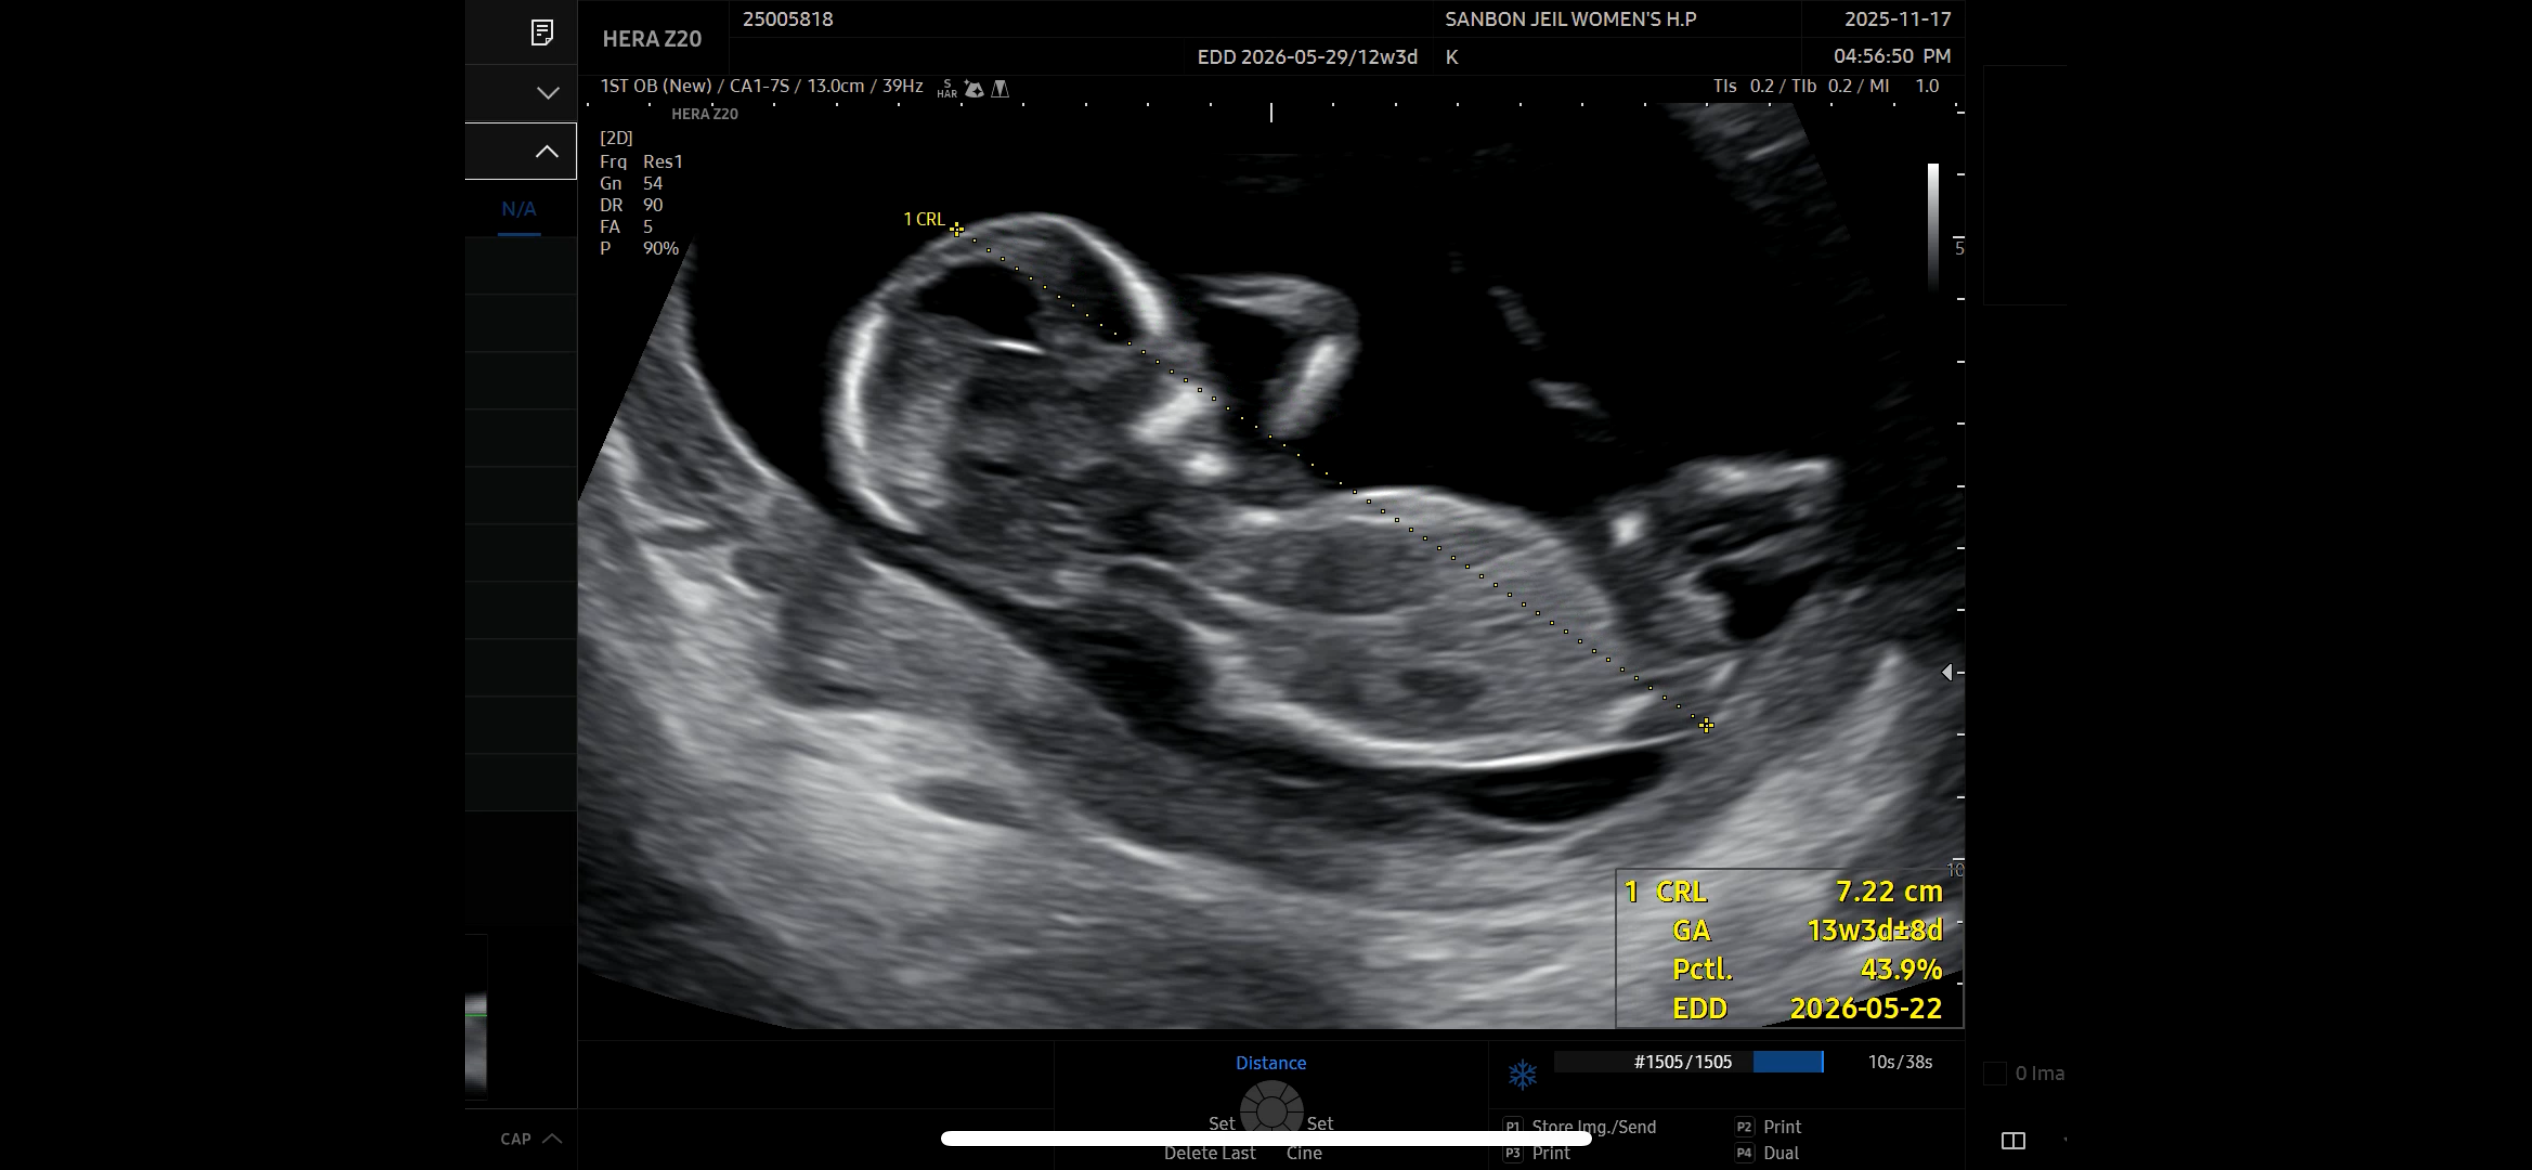

12주차에 찍었던 초음파인데 다리 사이에 뭔가 보이는데.. 혹시 아들일까요??